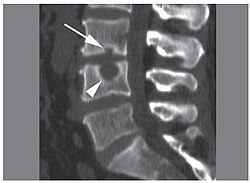

ŞMORL YIRTIĞI NƏDİR? Şmorl yırtığı, elmi adı ilə Schmorl’s node, onurğadakı fəqərəarası diskdən qığırdaq və ya disk daxilindəki pulpoz (jelly‑maddə) toxumasının yuxarı və...